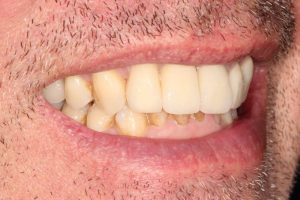

Full Mouth Rehabilitation

Full mouth Treatment – missing upper front teeth and mispositioned implants in the Lower left side meant planning was key here to get the desired result. Implants were placed to replace the missing teeth, veneers/crowns on the remaining upper teeth allowing an improvement in overall shape and colour, and the implant crowns on the lower left were change to bring into the line of the bite.